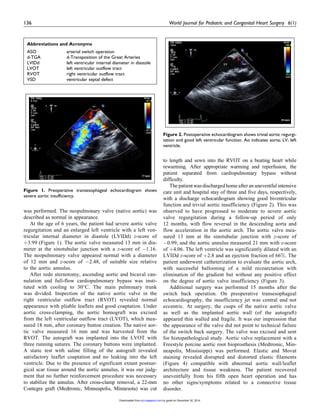

Figure 1. Preoperative transesophageal echocardiogram shows

severe aortic insufficiency.

At the age of 6 years, the patient had severe aortic valve

regurgitation and an enlarged left ventricle with a left ven-

tricular internal diameter in diastole (LVIDd) z-score of

þ3.99 (Figure 1). The aortic valve measured 13 mm in dia-

meter at the sinotubular junction with a z-score of À1.16.

The neopulmonary valve appeared normal with a diameter

of 12 mm and z-score of À2.48, of suitable size relative

to the aortic annulus.